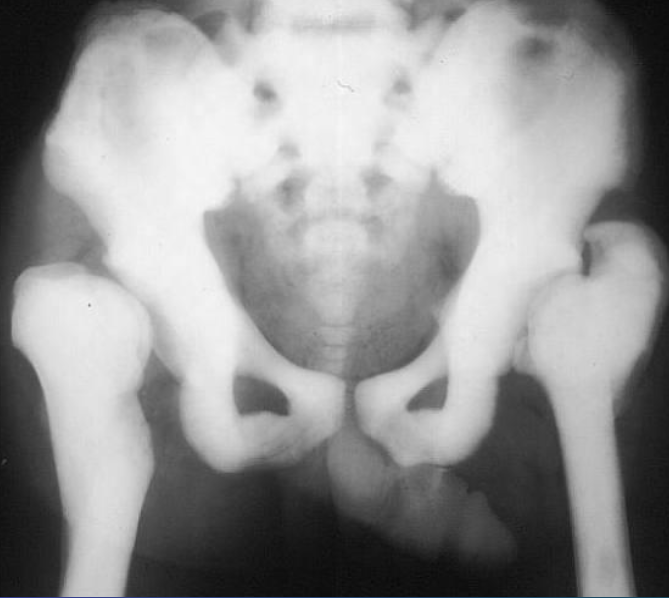

Pelvic ring fracture

X-ray pelvis (AP view)

Bilateral pubic ramus fractures are also present.